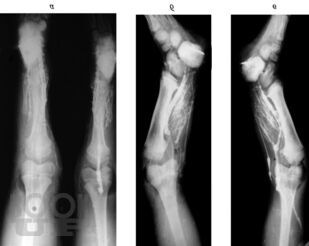

Врожденные пороки развития костей голени у детей

В монографии излагаются результаты многолетнихисследований, проведенныхв научно-исследовательском детском ортопедическом институте им. Г. И. Турнера. Рассматриваются вопросы клиники, диагностики и лечения врожденныхпороков развития костей голени у детей в возрасте от 3 мес. до 15 лет и старше. Описываются новые методики операций, основанные на сберегательной тактике, адекватные различным вариантам порока, позволяющие восстановить форму и функции конечности, техразновидностей порока развития костей голени, которые до настоящего времени считались неоперабельными и подлежали только ампутации. Монография предназначена для ортопедов, травматологов и хирургов.